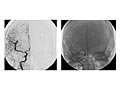

An angiogram of the head and neck is an X-ray test that uses a special dye and camera (fluoroscopy) to take pictures of the blood flow in the blood vessels of the head and neck. An angiogram of the neck (carotid angiogram) can be used to look at the large arteries in the neck that lead to the brain. An angiogram of the head (cerebral angiogram) can be used to look at the veins or the four arteries (four-vessel study) carrying blood to the brain.

During an angiogram, a thin, soft tube called a catheter is placed into a blood vessel in the groin or just above the elbow. The catheter is guided to the head and neck area. Then an iodine dye (contrast material) is injected into the vessel to make the area show clearly on the X-ray pictures. The angiogram pictures can be made into regular X-ray films or stored as digital pictures in a computer.

An angiogram can find a bulge in a blood vessel (aneurysm). It can also show narrowing or a blockage in a blood vessel that slows or stops blood flow. An abnormal pattern of blood vessels (arteriovenous [AV] malformation) or abnormal vessels near a tumor can be seen.